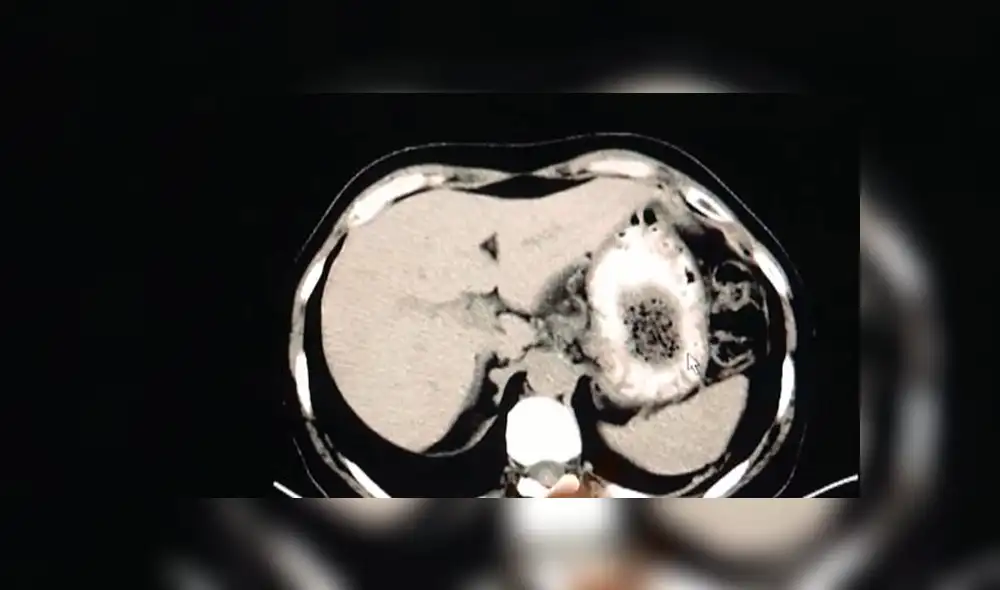

El gastroenterólogo residente del centro de salud, Zhu Zhen, explicó que los escáneres mostraban una sombra en el estómago de la paciente, y era difícil identificar de qué se trataba, por lo que decidieron realizarle otros exámenes.

Una endoscopia posterior reveló que se trataba de un bezoar gigante, que estaba obstruyendo el estómago y le causaba los dolores debido a su gran tamaño.

Un bezoar es una masa sólida de material no dirigible que se acumula en el tracto digestivo, lo que puede causar un bloqueo, de acuerdo con MayoClinic. Por lo general, se forman en el estómago, pero también puede aparecer en el intestino delgado o grueso.

Zhu Zhen explicó que el bezoar de la señora Zhang se había formado como resultado de su dieta que consistía en frutas de caqui y carne de cangrejo.

“Para los pacientes cuyo sistema digestivo ya es débil, comer muchos caquis y muchos cangrejos en un corto período de tiempo puede conducir a la formación de bezoares debido a una combinación de proteínas y ácidos tánicos”, agregó Zhen.

El galeno le recetó una terapia de ondas de choque con ultrasonido para ayudar a romper la masa debido que es mucho menos invasivo que la cirugía y no causaría efectos adversos, informó Asia Wire.